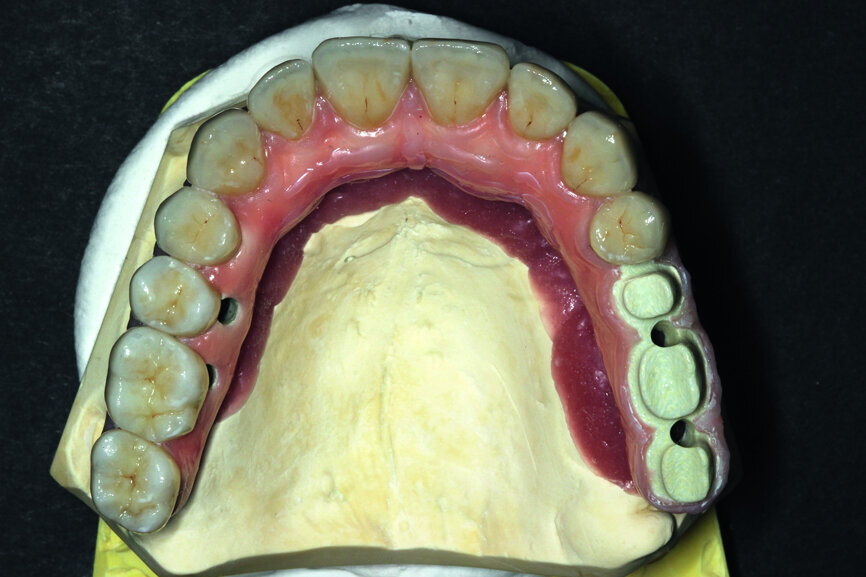

Fig. 11: Suprastructure cut out and transferred onto the model.

Fig. 12: Test of the construction within the oral cavity—visible opening for screws.

In order to prepare the bridge, a model was scanned and transferred onto a computer using software to design the bar (Fig. 1). The bar was designed by using special software in such a way that the whole design was transparent in the first phase so that the location of abutments and the position of the telescopic abutments at the frontal section could be visible (Fig. 2).